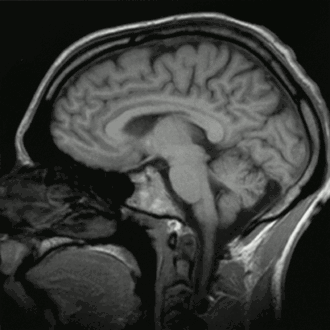

![]() Cortes sagitales del contenido intracraneal humano normal. | ||